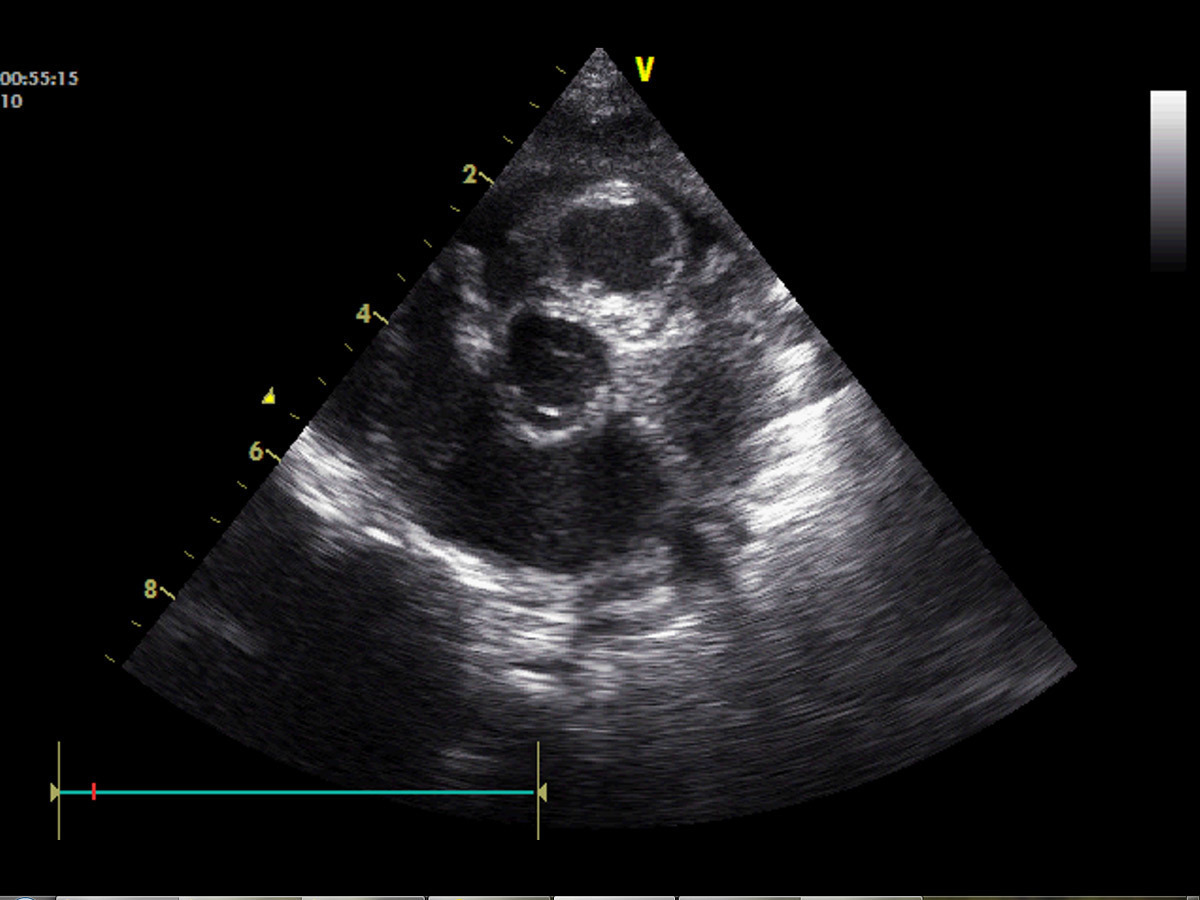

Certaines cardiopathies ne soufflent pas, d’autres soufflent plus tardivement (communication interventriculaire [CIV] par exemple)